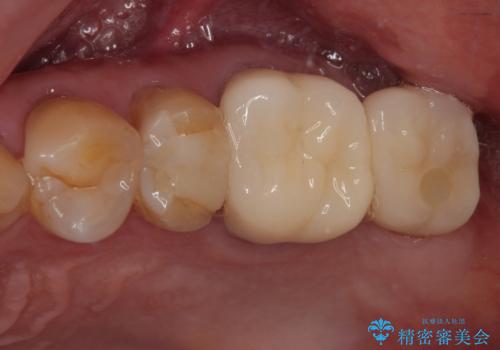

右下の銀歯が外れた オールセラミッククラウン

担当医 有澤哲郎